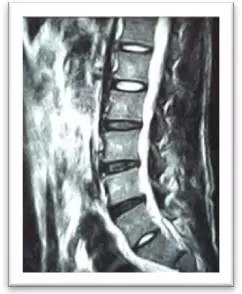

(術后)

摘除后,患者即感左下肢酸脹消失,直腿抬高試驗陰性,2天后即可下地行走,術后10天拆線出院。小姚對療效非常滿意。